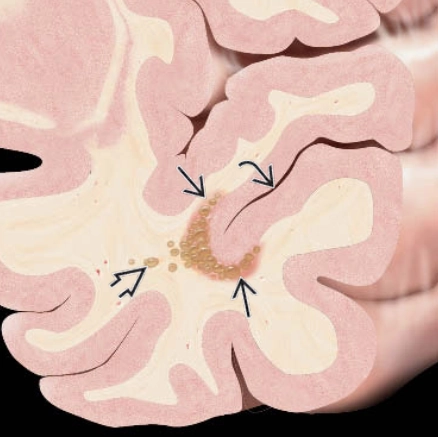

U thần kinh đa nốt và tạo không bào (Multinodular and vacuolating neuronal tumors - MVNT)